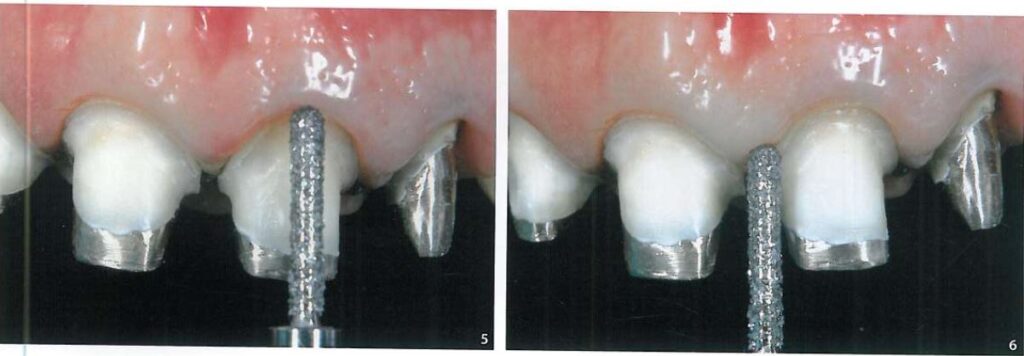

Sau đó dùng mũi khoan mài điều chỉnh tiếp đường hoàn tất nếu cần (H6).

Sợi chỉ thứ 2, với kích thước lớn hơn (chỉ Ultrapak #2, Ultradent) đặt vào khe nướu để tách mô nướu sang bên, chỉ này không nhất thiết phải nằm hoàn toàn trong khe nướu mà có thể chỉ nằm trên bề mặt (H7, 8).